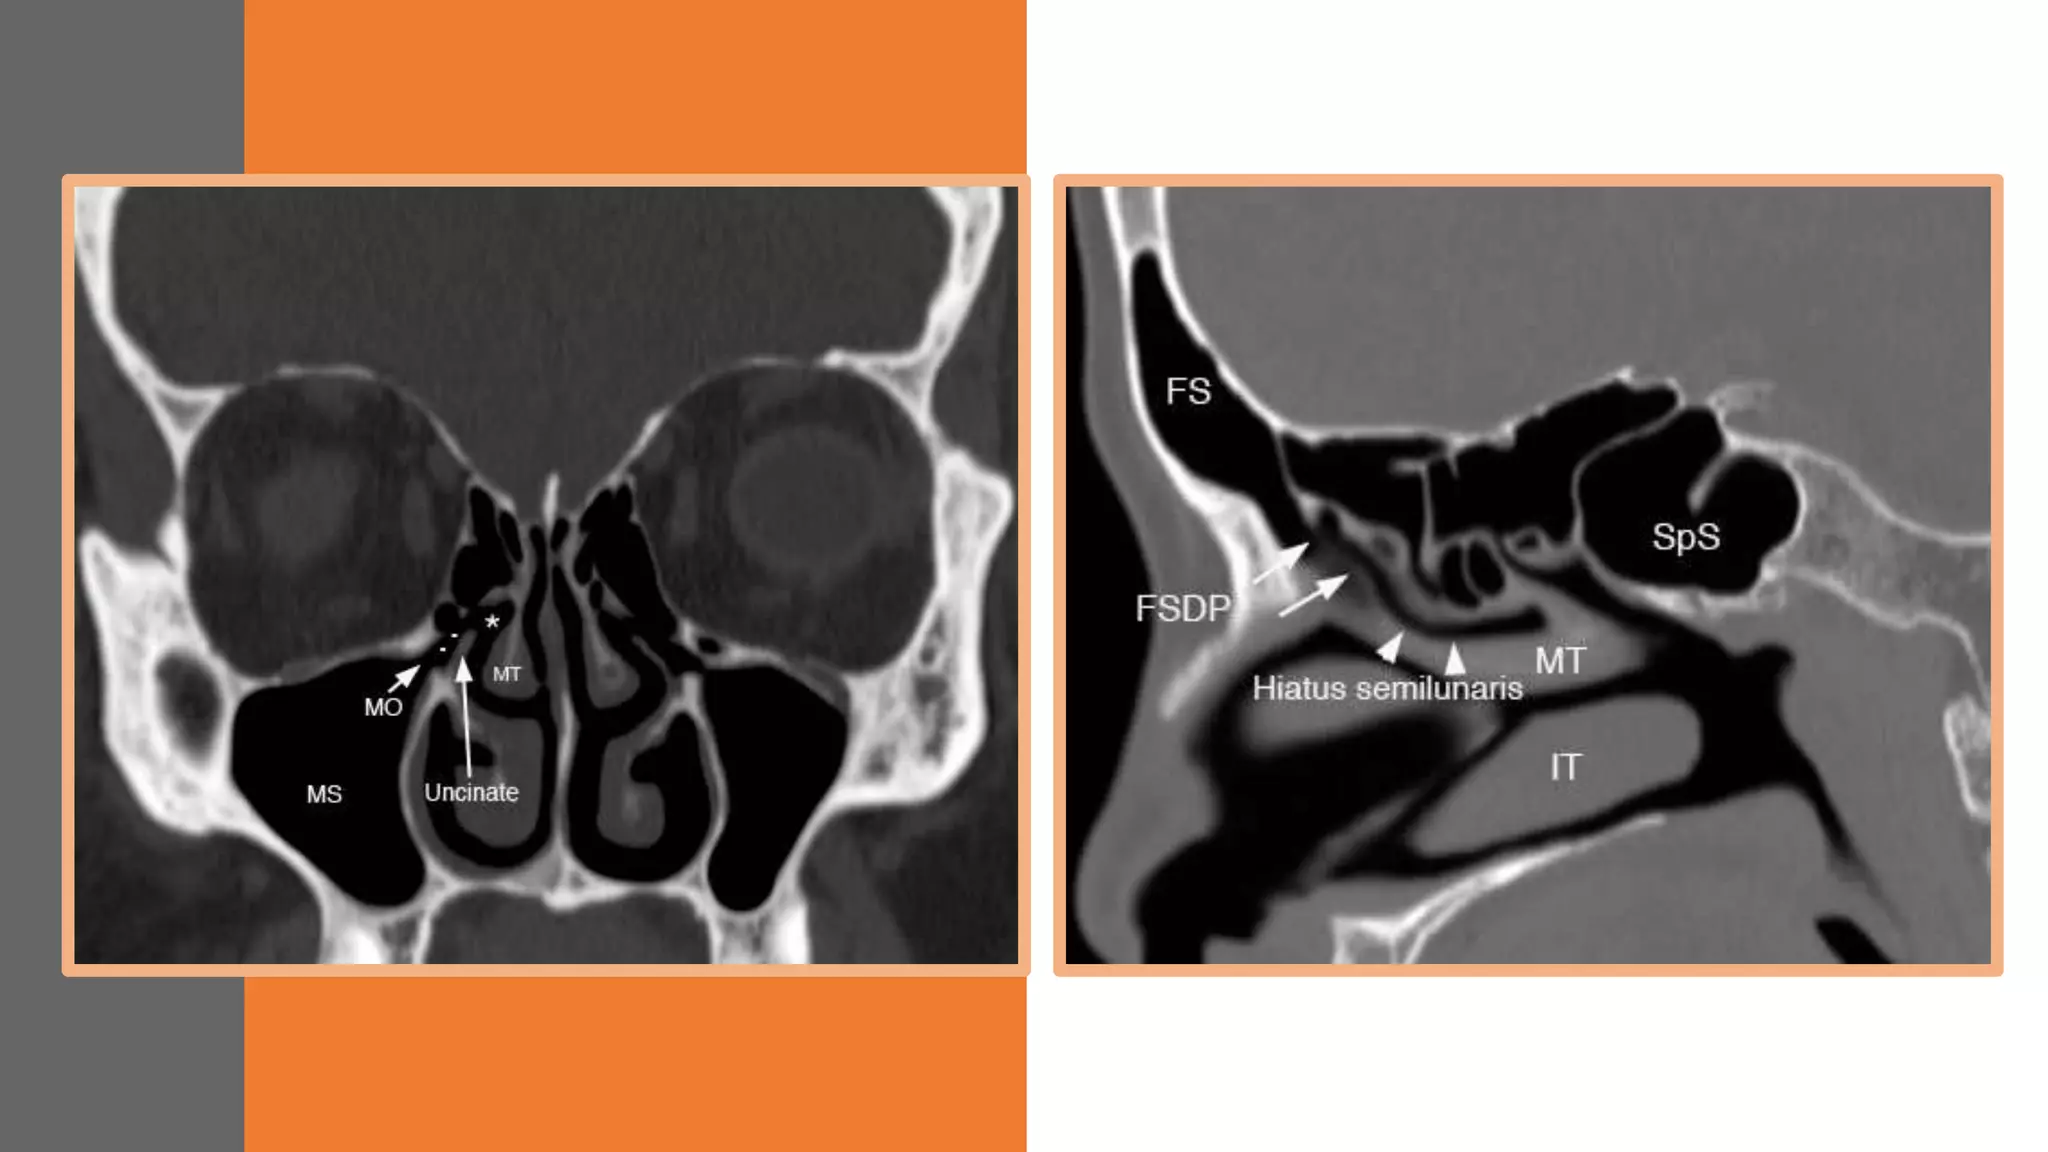

OSTEOMEATAL COMPLEX

BOUNDARIES

• Medially :middle turbinate,

• Posteriorly and superiorly : basal

lamella

• Laterally : lamina papyracea.

• Inferiorly and anteriorly the omc is

open.

STRUCTURES

• Maxillary sinus ostium

• Ethmoidal bulla

• Frontal recess

• Uncinate processus

• Infundibulum

• Hiiatus semilunaris

• Middle meatus

DRAINING PATHWAYS

NORMAL ANATOMY

ANTERIOR DRAINING PATHWAYS

• Osteomeatal complex – air passage between

frontal , ant ethmoid and maxillary sinus

Components: Frontal recess , ethmoid

infundibulum , hiatus semilunaris and middle

meatus

MIDDLE MEATUS

• b/w middle turbinate and uncinate process

• Uncinate process: superior extension of the

medial wall of maxillary sinus

• Agger Nasi : Most anterior cells in ant

ethmoidal sinus complex

• Hiatus semilunaris – Crevice between

uncinate process and ethmoidal bulla

• Ethmoidal infundibulum : maxillary ostium

to middle meatus , b/w uncinae process and

lamina papyracea